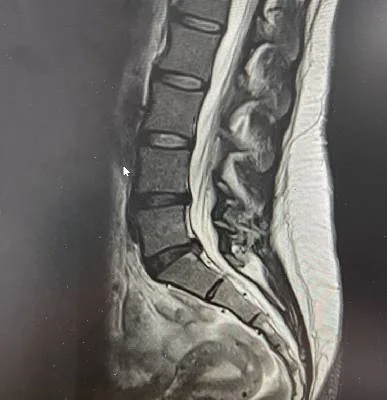

Dr. Haytham Elkhatib is a distinguished orthopaedic surgeon specializing in comprehensive musculoskeletal care. With expertise in trauma, fracture treatment, and advanced interventional joint injections, he offers innovative solutions for various conditions.

Orthopedic care is never a solo act. At our clinic, we work as a multidisciplinary team – combining surgical expertise, physiotherapy, radiology, and patient support – to deliver personalized care plans that lead to the best outcomes.